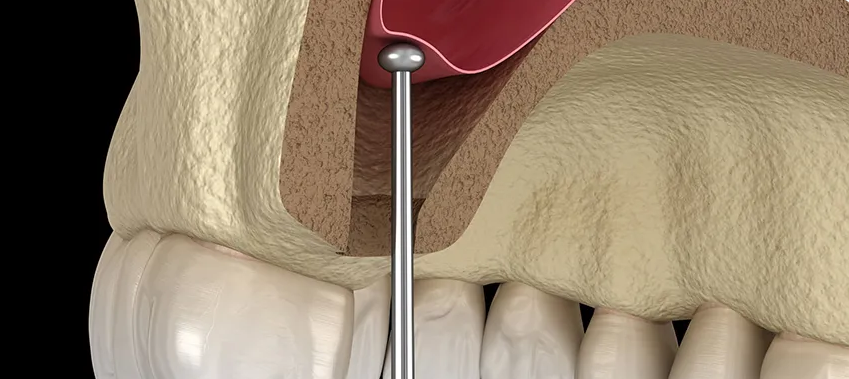

رفع الجيوب الأنفية

تمكين الزراعة في الفك العلوي

إجراء متخصص لرفع أرضية الجيب الأنفي لتوفير ارتفاع عظمي كافٍ في الفك العلوي لنجاح زراعة الأسنان.

الطريقة من القمة

طريقة طفيفة التوغل لاحتياجات العظم المتوسطة

زراعة متزامنة

رفع الجيب وزراعة الأسنان في آن واحد عند الإمكان